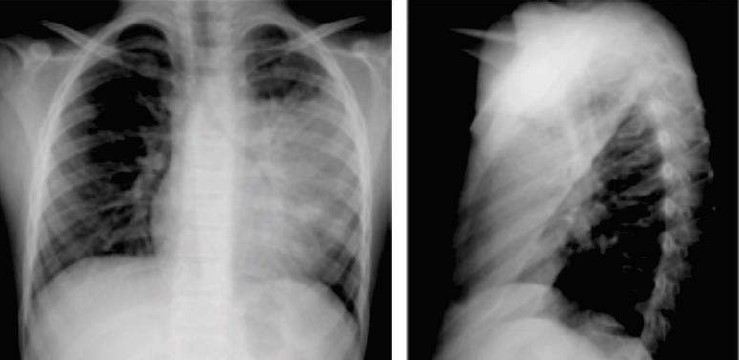

Um paciente de 36 anos de idade procurou atendimento médico queixando-se de tosse produtiva com escarro purulento, febre alta com calafrios e dor pleurítica à esquerda. Negou comorbidades e tabagismo. Ao exame físico, observava-se PA de 121 x 79 mmHg, FC de 106 bpm, FR de 23 irpm, Sat. de o2 de 94% em ar ambiente, com temperatura axilar de 38,8 ⁰C. O exame do tórax registrou a presença de murmúrio vesicular reduzido à esquerda. O hemograma mostrou leucocitose de 18.000 com 4% de bastões, sendo que eletrólitos e função renal e hepática estavam normais. A radiografia de tórax obtida na admissão é a seguinte:

Com base nesse caso hipotético, assinale a alternativa correta: